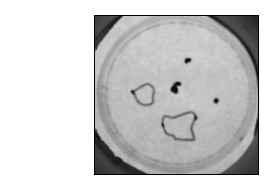

Low magnification picture from a Petri dish in which 5 explants are initially placed. 3 weeks after, 3 explants, marked with a dot, were not able to produce an efficient innervation and the 2 latter explants innervated large muscle areas which were delimited by a line.

BDNF at 10 ng/ml increases the innervate rate from 20% under control condition to 25% with BDNF and augments the surface of skeletal muscle innervated by an efficient rat spinal cord-human muscle coupling.